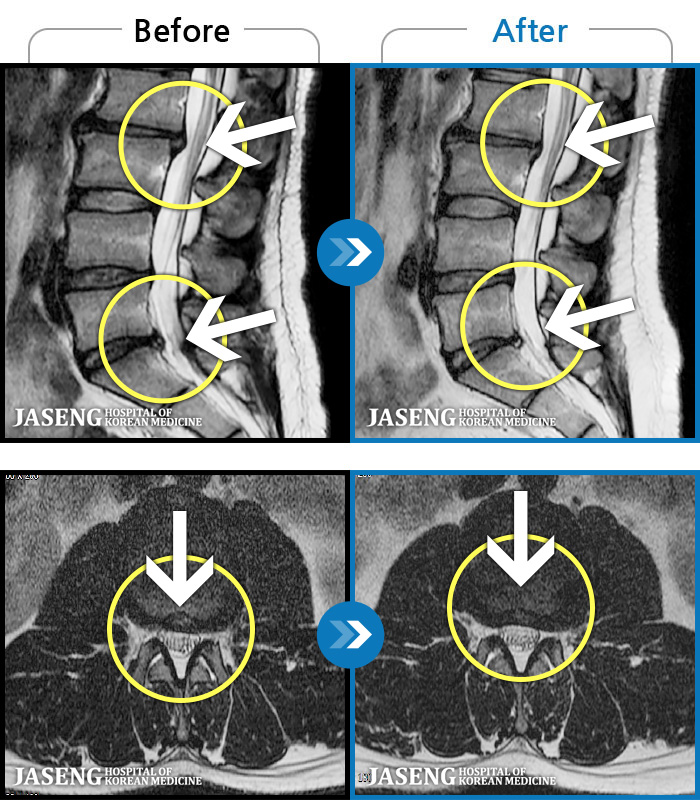

MRI ġ

1,304 MRI ũ ʸ Ȯϼ.